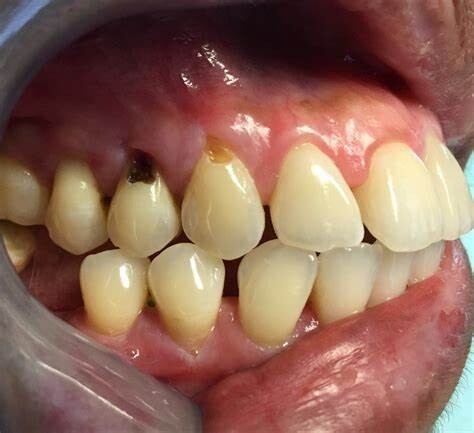

Gumline cavities can also be associated with exposed tooth roots. Gum tissue usually protects the roots, but the roots will be vulnerable if the gum tissue recedes. That's because roots are covered in a material called cementum, which is much weaker than tooth enamel.

Tooth decay – Without the protective covering of gum tissue, exposed tooth roots become much more vulnerable to invasion by decay-causing oral bacteria. Plaque and tartar can readily adhere in these areas, leading to cavities.

Tooth sensitivity – Once the cementum layer of the root surface is exposed due to receded gums, the openings to underlying dentinal tubules become exposed as well. This allows hot, cold, or acidic foods to stimulate the nerves and fluid within the tubules, causing sharp pains and sensitivity.

Root cavities – Once gum recession occurs, cavities at the gumline and beneath the gums can form. These subsurface lesions are more difficult to detect, treat, and restore.